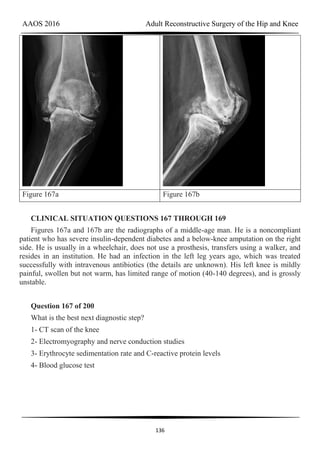

transfusion rates. Inconclusive evidence shows that IV administration of TXA places

individuals at higher risk for a thromboembolic event. Both IV and topical TXA are equally

effective in decreasing blood loss and minimizing transfusion rates.

AAOS 2016 Adult Reconstructive Surgery of the Hip and Knee

60

Figure 74a Figure 74b Figure 74c

Question 74 of 200

Figures 74a through 74c are the postsurgical radiographs of a 74-year-old man who has

stiffness in his right knee 8 weeks after undergoing elective right total knee arthroplasty

(TKA). The surgery was performed for primary varus osteoarthritis and was uncomplicated.

His range of motion is 5 to 80 degrees. What is the most appropriate next treatment step?

1- Manipulation under anesthesia (MUA)

2- Arthroscopic lysis of adhesions

3- Open arthrolysis of adhesions

4- Revision TKA

PREFERRED RESPONSE: 1- Manipulation under anesthesia (MUA)

DISCUSSION

Stiffness following TKA is a disabling complication. One option involves MUA, a

valuable technique with which to increase range of motion after TKA for patients with stiff

knees. A systematic review of the literature was performed to identify studies that reported the

clinical outcomes and measured range of motion for patients undergoing MUA. Fourteen

studies (913 patients) reported range of motion results following MUA at up to 10-year follow-

up. The review demonstrated that MUA for a stiff primary TKA is an efficacious procedure to

restore range of motion, and it carries a low complication rate. Early gains in motion were

61

reported to be maintained in the long term. A second review systematically evaluated the

outcomes of 4 treatments for arthrofibrosis that develops subsequent to TKA (MUA,

arthroscopic debridement, open surgical release, and revision TKA). This study showed that

there were no significant differences in the Knee Society Score of the 4 treatment modalities.

Although open surgical release resulted in the greatest increase in range of motion, there were

methodological study limitations because the majority of the papers were case series, which

decreased the quality of the evidence. Response 1 is correct because the TKA appears

appropriately sized and is well aligned. Responses 2 and 3 are incorrect, considering the early

time frame (8 weeks) from initial surgery. Although the patella is unresurfaced in the

radiographs, there is no indication for revision TKA (even secondary patellar resurfacing) at

this early juncture.

Question 75 of 200

During total hip arthroplasty, which characteristic of irradiated (10 Mrad) and

subsequently melted highly cross-linked polyethylene should provide a more wear-resistant

construct than traditional gamma-irradiated (2.5-4 Mrad)-in-air polyethylene mated with the

same head?

1- Resistance to adhesive wear

2- Resistance to abrasive wear

3- Resistance to fatigue wear

4- Resistance to creep

PREFERRED RESPONSE: 1- Resistance to adhesive wear

Highly cross-linked polyethylene makes material resistant to adhesive wear. Abrasive

wear from third bodies does not decrease wear. The fatigue strength of this material is inferior

to traditional polyethylene, and its resistance to creep is the same, if not lower, than that of

traditional polyethylene.

62

Figure 76a Figure 76b

Figure 77a Figure 77b

63

Figure 78a Figure 78b

Figure 79a Figure 79b

64

Figure 80a Figure 80b

RESPONSES FOR QUESTIONS 76 THROUGH 80

1- Cemented full revision

2- Cemented femoral revision

3- Cemented acetabular revision

4- Cementless full revision

5- Cementless femoral revision without an extended trochanteric osteotomy

6- Cementless femoral revision with an extended trochanteric osteotomy